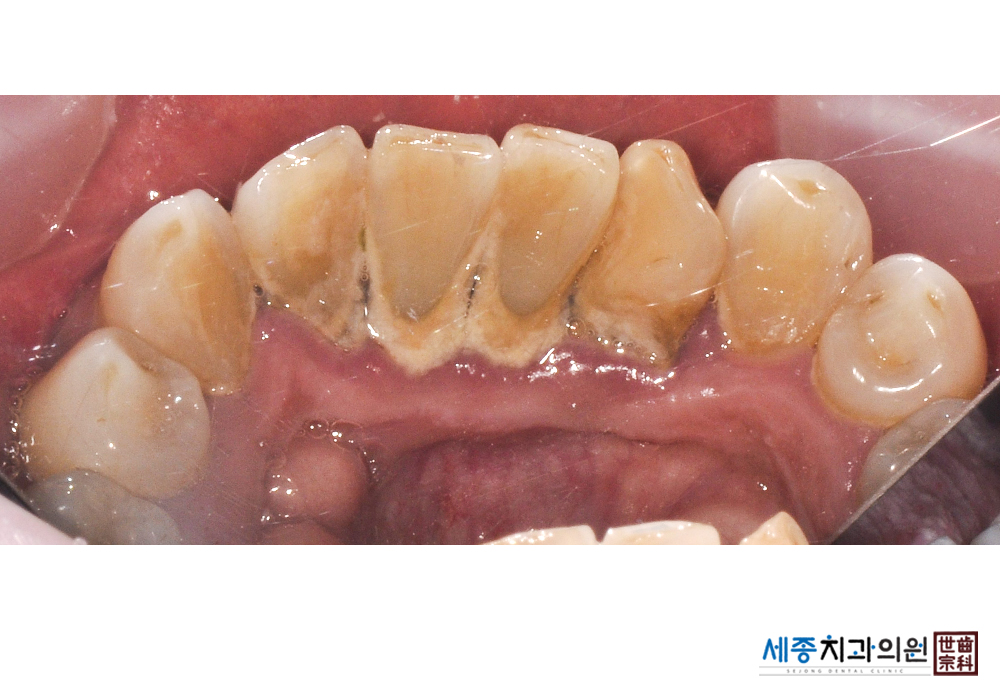

[스케일링] 치주질환 예방 스케일링 치료

치료전 : 2019-01-31

치료후 : 2019-01-31

가글마취&저주파 스켈러를 사용한 스케일링